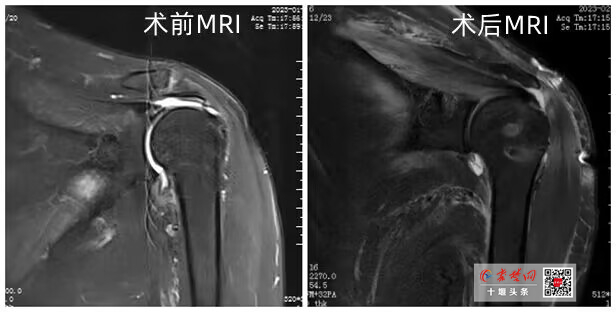

王全兵接诊后,初步判断周大爷是肩袖损伤,磁共振检查验证了他的判断,并确定老人已达到巨大肩袖损伤的程度。王全兵介绍,肩袖是由冈上肌、冈下肌、肩胛下肌、小圆肌肌腱分布在肩关节前、后、上方包绕肩关节形成的袖套样的组织。每一根肌腱都在肩关节内收、外展、前屈、后伸、上举、环转中起到重要作用,任何一根肌腱损伤,其所对应的功能则明显减弱,肌腱损伤就造成了肩袖损伤。

针对周大爷的情况,王全兵团队采取肩袖缝合、肌腱转位等方式,在肩关节镜下,通过微创手段,先对萎缩的肌腱进行松解,让肌腱尽可能复位,然后予以缝合,对不能完全复位的肌腱采用肌腱转位固定。两个小时后,手术完成,周大爷肩关节疼痛立刻得到缓解,在他人的帮助下可以实现手臂自由活动。